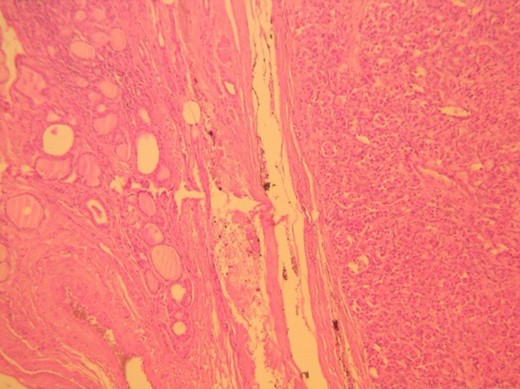

Histologic examination showed a 34 × 26 mm tumor on the left lobe which consisted of neoplastic cells nests arranged in a characteristic ‘zellballen’ pattern (Figs 1 and 2). Immunohistochemistry was positive for neuroendocrine markers (Chromogranin A, Synaptophysin, CD56, NSE, CD 57) and negative for cytokeratins (AE1/AE3, 7, 8, 19), Calcitonin, CEA and Thyroglobulin (Figs 3–5).

H&E ×100, original magnification. Tumor is shown to the right, circumscribed and surrounded by a thin fibrous capsule (arrows).